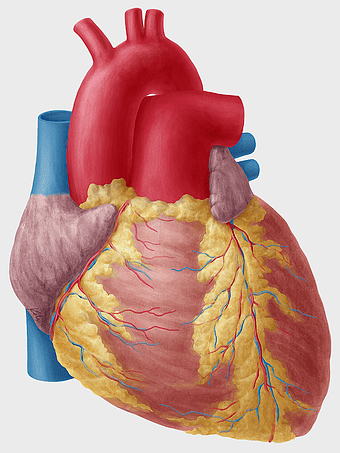

human heart diagram, cardiovascular system anatomy, blood vessel chart, free body diagram, circulatory system illustration, medical organ visualization, human anatomy study -

human heart anatomy, cardiac muscle illustration, circulatory system model, heart health visual, cardiovascular organ diagram, medical heart image, visceral structure depiction -

heart anatomy illustration, cardiovascular system diagram, circulatory system medical, vascular system sonography, human body blood flow, arterial network visualization, heart function analysis -

human heart illustration, cardiac anatomy diagram, heart blood vessels, medical organ visuals, cardiovascular system chart, human anatomy study, circulatory system illustration -

Heart Anatomy Atrium, Aortic arch Human body, human circulatory system, ventricle and heart阀, cardiovascular health, thoracic cavity structures, heart valve functionality, atrium blood flow diagram -